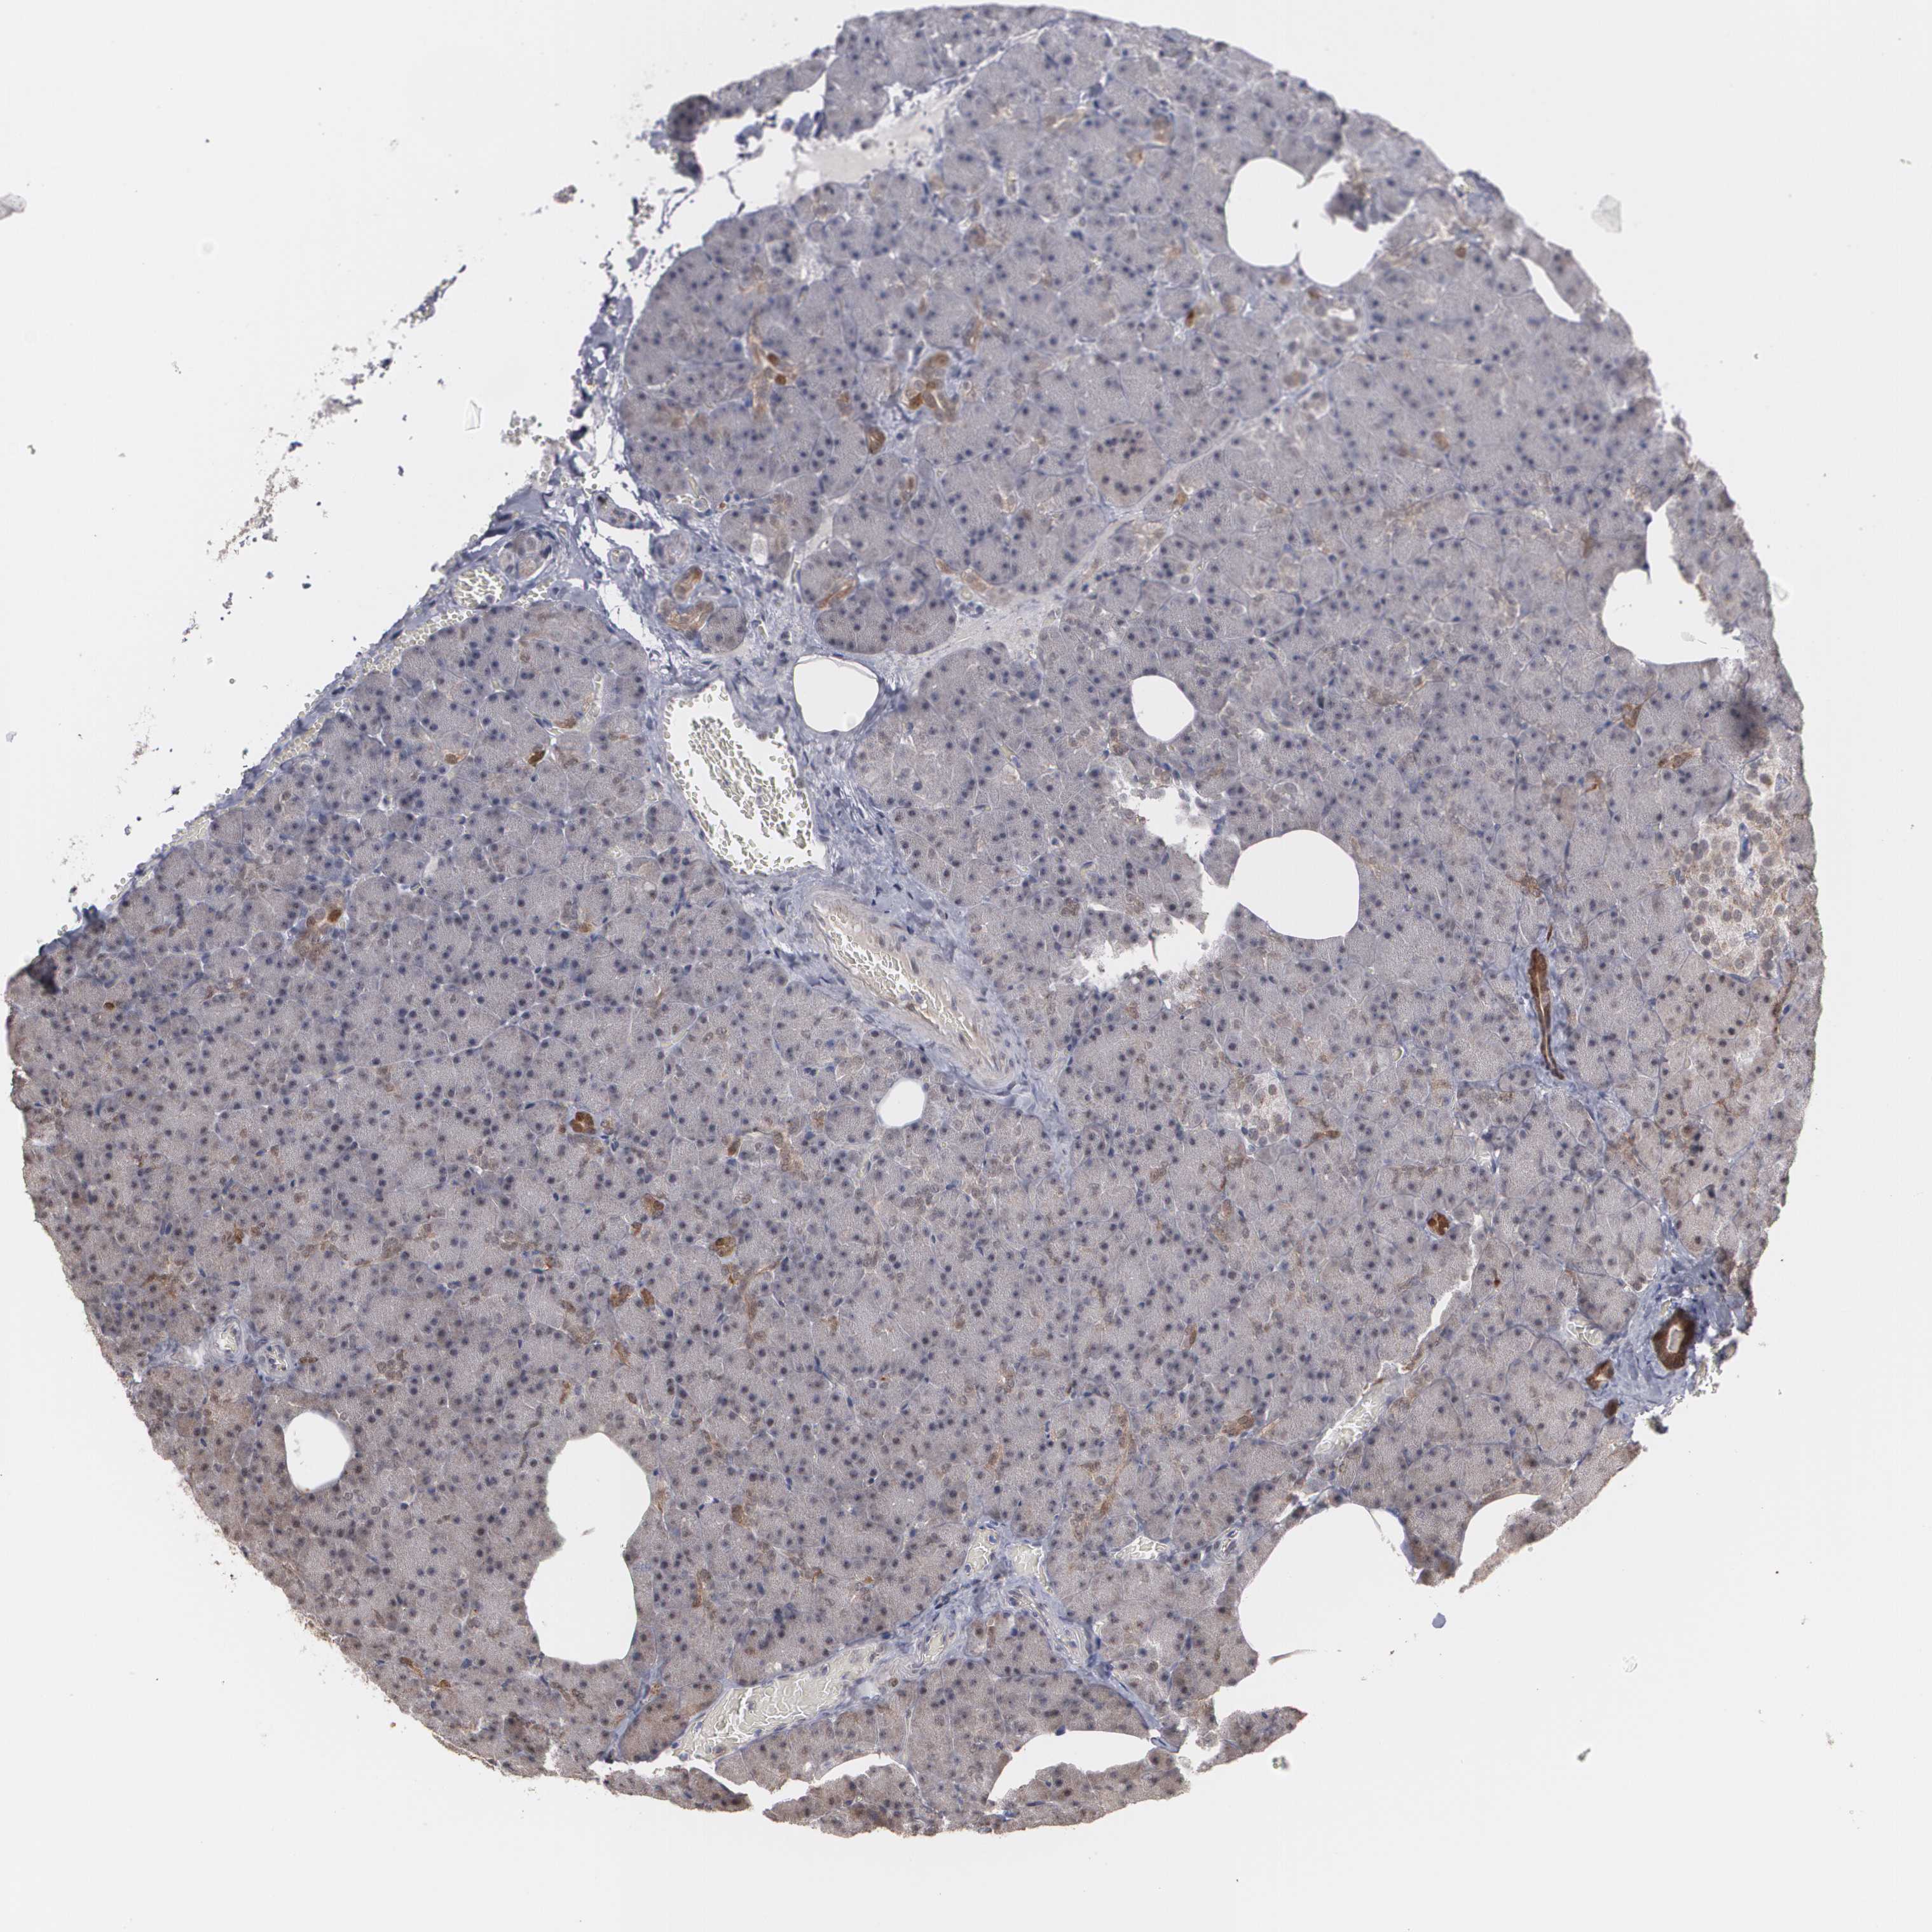

CARCINOID - Protein expressioni

A mouse-over function shows sample information and annotation data. Click on an image to view it in a full screen mode. Samples can be filtered based on level of antibody staining by selecting one or several of the following categories: high, medium, low and not detected. The assay and annotation is described here.

Antibody staining in the annotated cell types in the current human tissue is reported as not detected, low, medium, or high, based on conventional immunohistochemistry profiling in selected tissues. This score is based on the combination of the staining intensity and fraction of stained cells.

Each image is clickable and will lead to virtual microscopy that enables deeper exploration of all samples and also displays staining intensity scores, fraction scores and subcellular localization as well as patient and tissue information for each sample.

Antibody HPA001665

Carcinoid, malignant, NOS